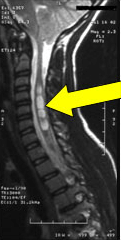

There is a particularly high incidence of Arnold-Chiari malformation, of Syringomyelia (cyst in the spinal cord (Figure), or generally of a neuromuscular disease, when the respective scoliosis will be marked as neuromuscular and as such will be handled.